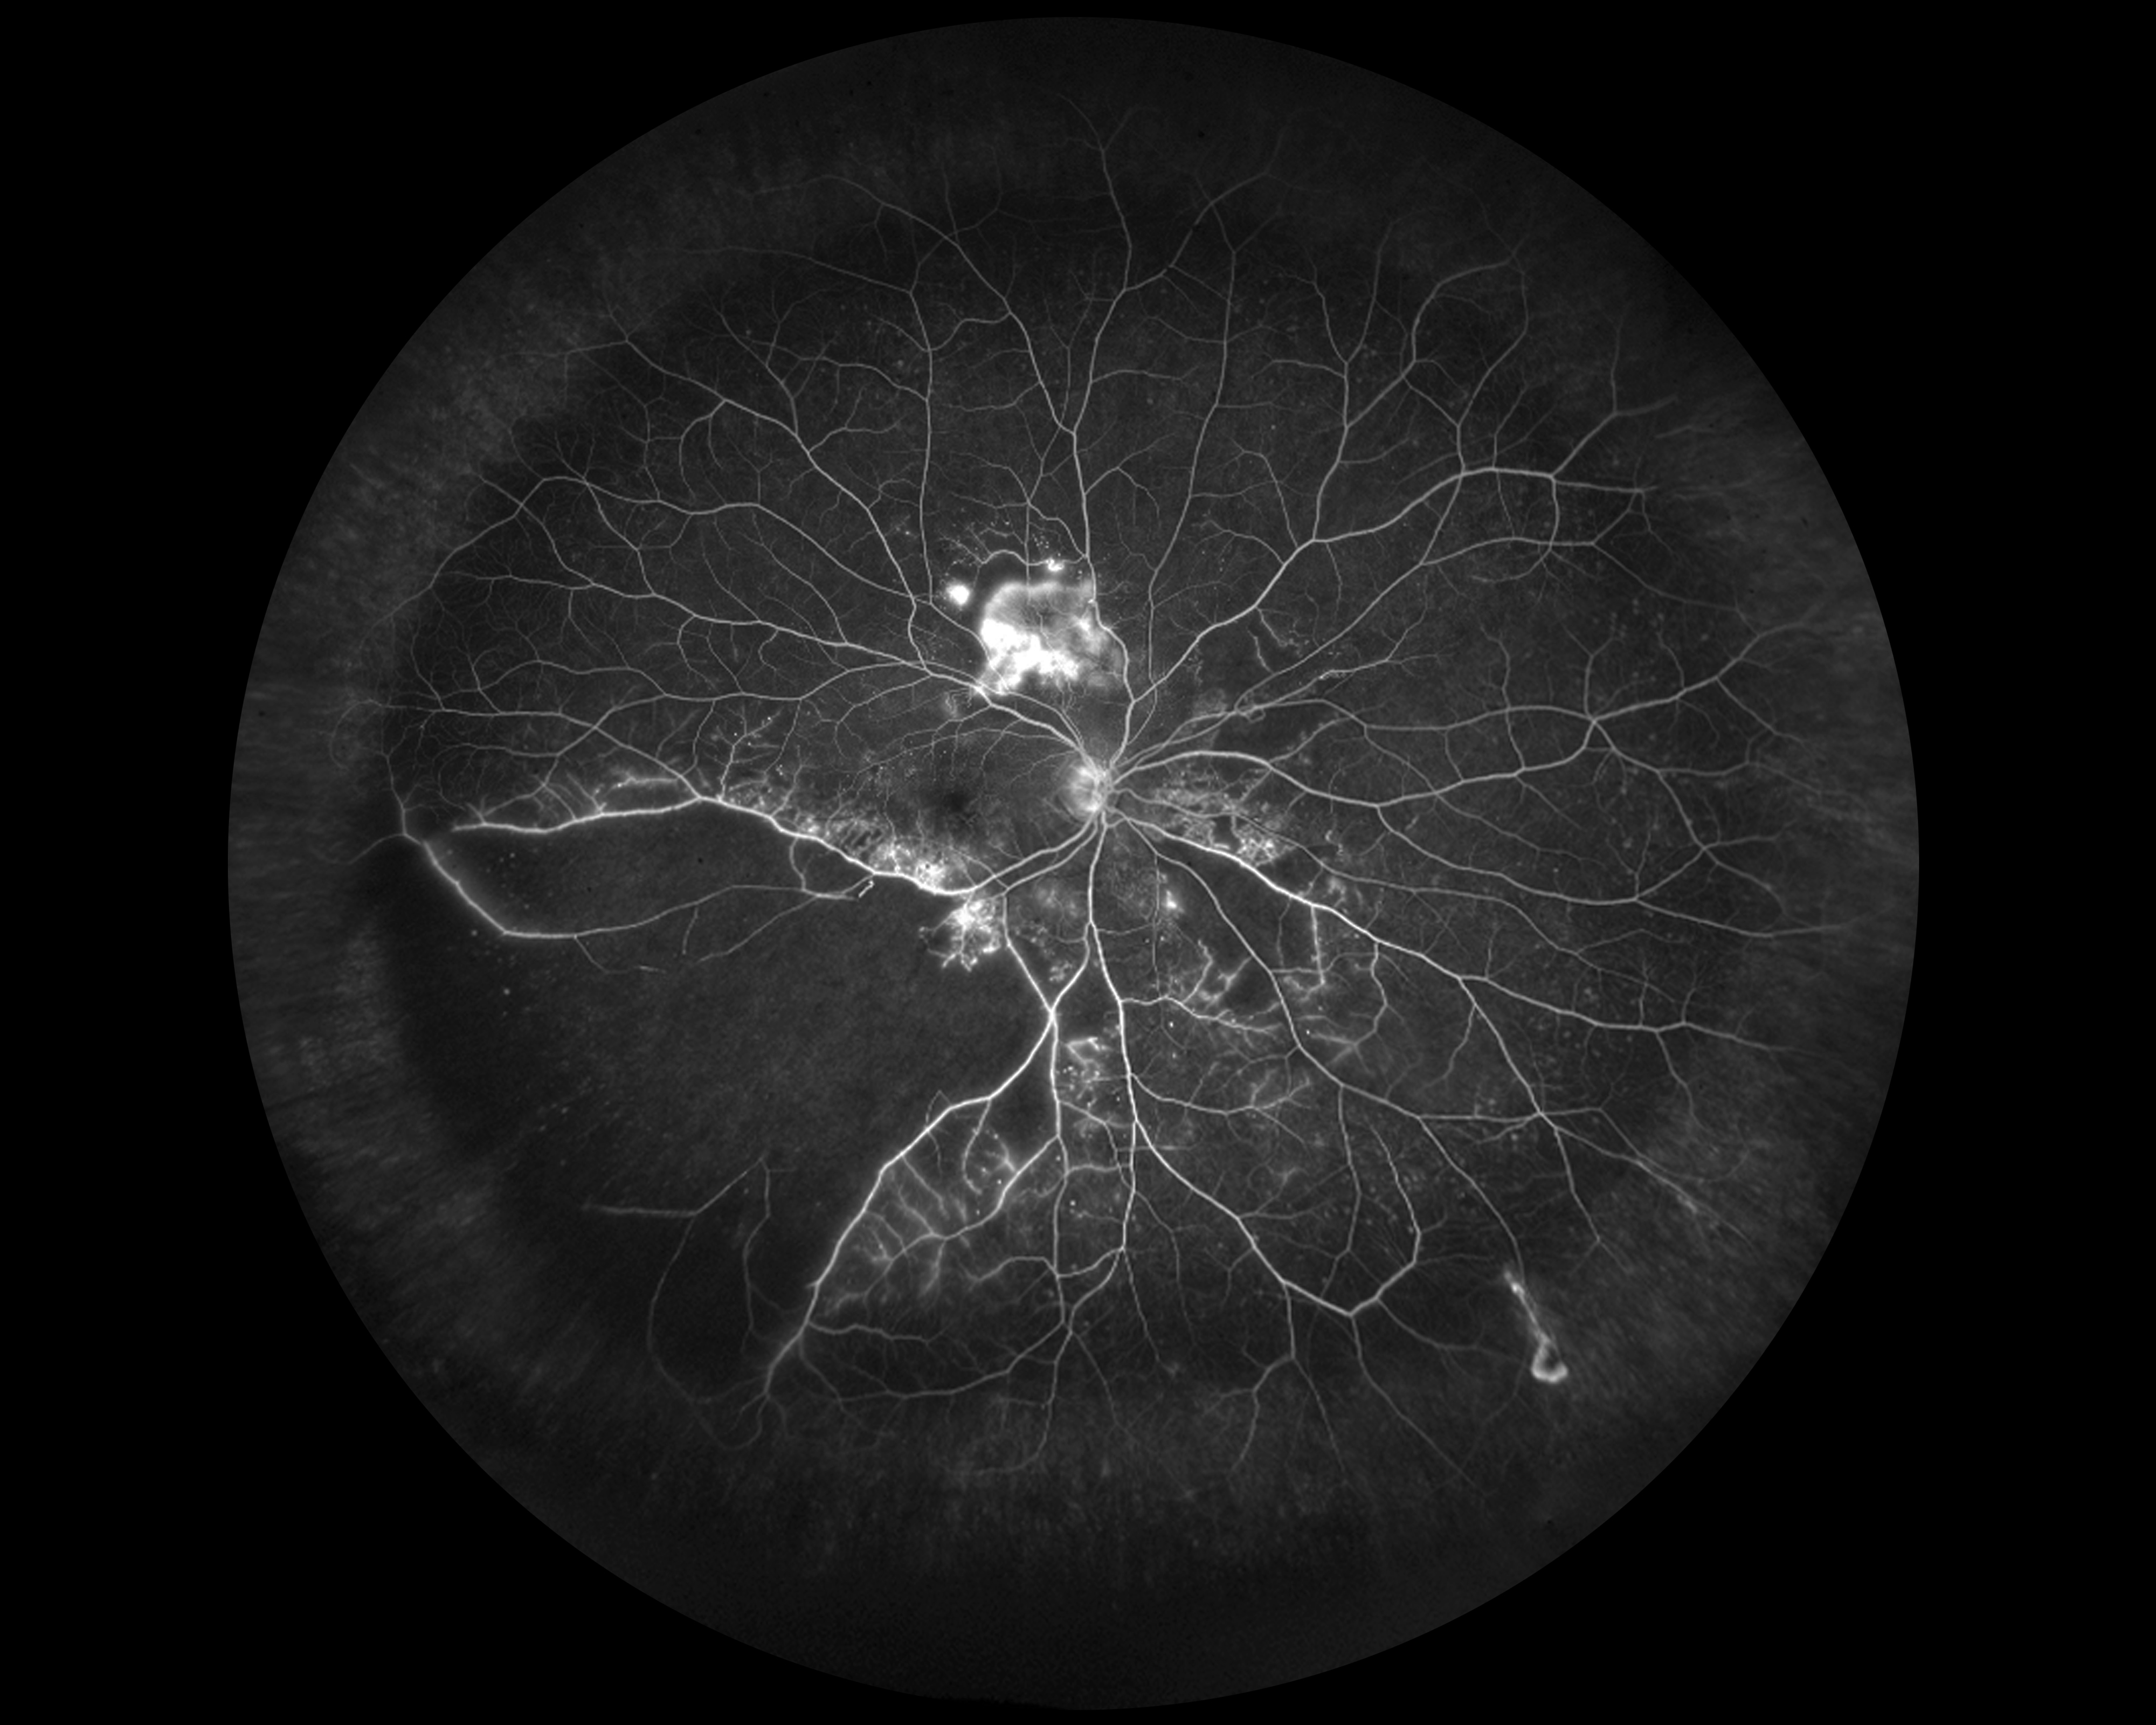

Branch Retinal Vein Occlusions Presented by Kasi Sandhanam This photograph received First Place, Composite in the 2025 OPS Scientific Exhibit. Filed Under Retina OPS Photo